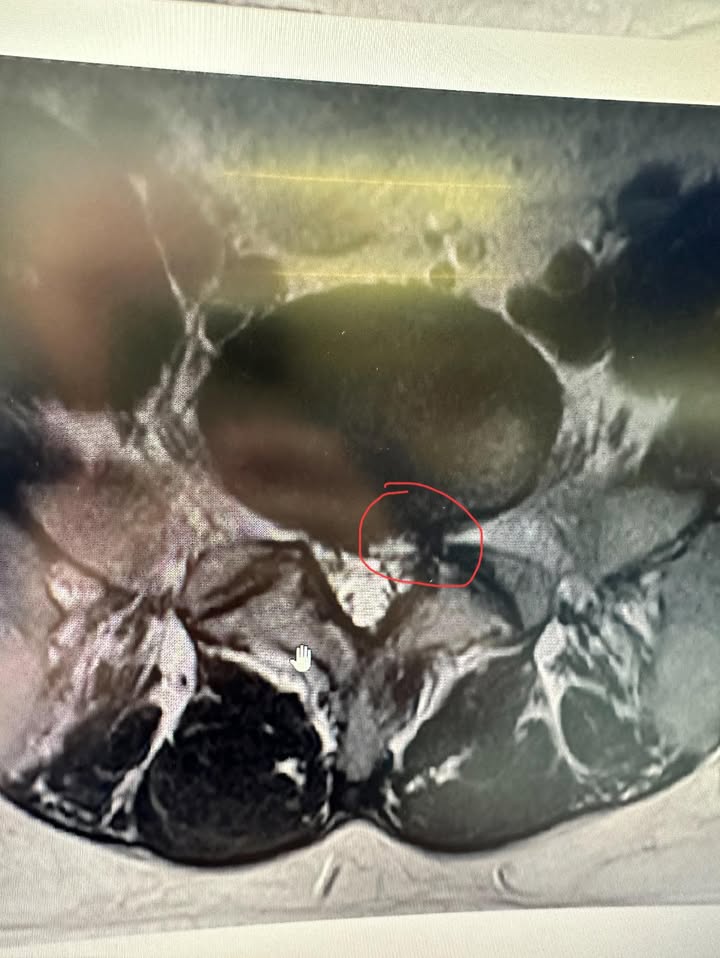

懷著最後的希望,楊生終於踏上了前往台北的旅程。當他推開診室的門時,跟我述說他這些年的病痛,我很仔細地詢問他的感受,並且看完他所有核磁共振報告跟檢查,並且安慰他還不是很嚴重可以不用急著開刀!我相信讓醫療團隊這種貼心的態度,讓楊先生一顆焦躁的心慢慢地沉靜下來,彷彿不再是病痛纏身的自己,而是被看見、被照顧的個體。